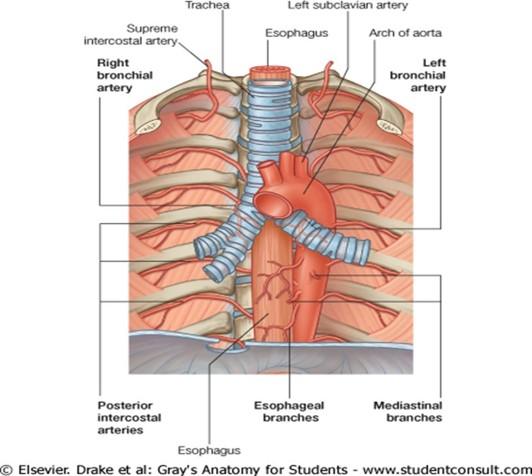

the bronchial arteries come from where? what will you commonly see with these?

from the aorta

you will see them coming from variable pathways from the aorta

in this person, what bronchial arteries can you point out?

you can point out the right bronchial artery and then on the other side, the left superior bronchial artery and the left inferior bronchial artery both going to the same bronchi tube on bottom

Bronchial veins:

- Right bronchial vein drains into the _____________?

- Left bronchial vein drains into the _______________?

azygos vein

accessory azygos vein

in picture, you can see the azygos vein on the left and the small vessel (right bronchial vein) draining into the azygos

on the other side you see the small left bronchial vein draining into the accessory hemi-azygos